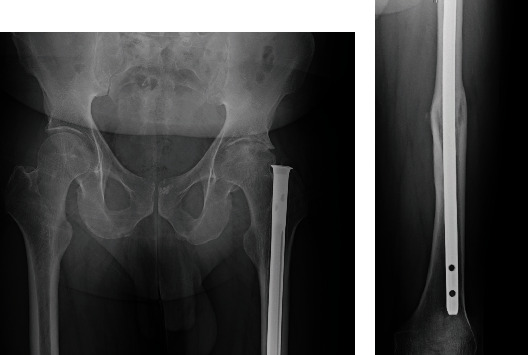

This paper presents a surgical technique for the removal of an old universal femoral nail preceding total hip arthroplasty (THA) in a 50-year-old male patient with left hip osteoarthritis. The patient had undergone femur nail insertion approximately 35 years ago. Due to the necessity of nail removal prior to THA, surgery to remove the nail was planned. There are challenges posed by the design of the old universal femoral nail system, particularly its side slot which made engagement of the conical bolt difficult. The successful removal of the nail was eventually achieved, enabling subsequent THA. Individuals who received this old implant years ago may now require its removal as part of osteoarthritis treatment. Given the lack of familiarity among surgeons with this outdated implant, this paper is aimed at providing essential guidance and insights regarding its removal procedure. This literature represents the inaugural documentation of the surgical technique for the removal of an aged femur nail.